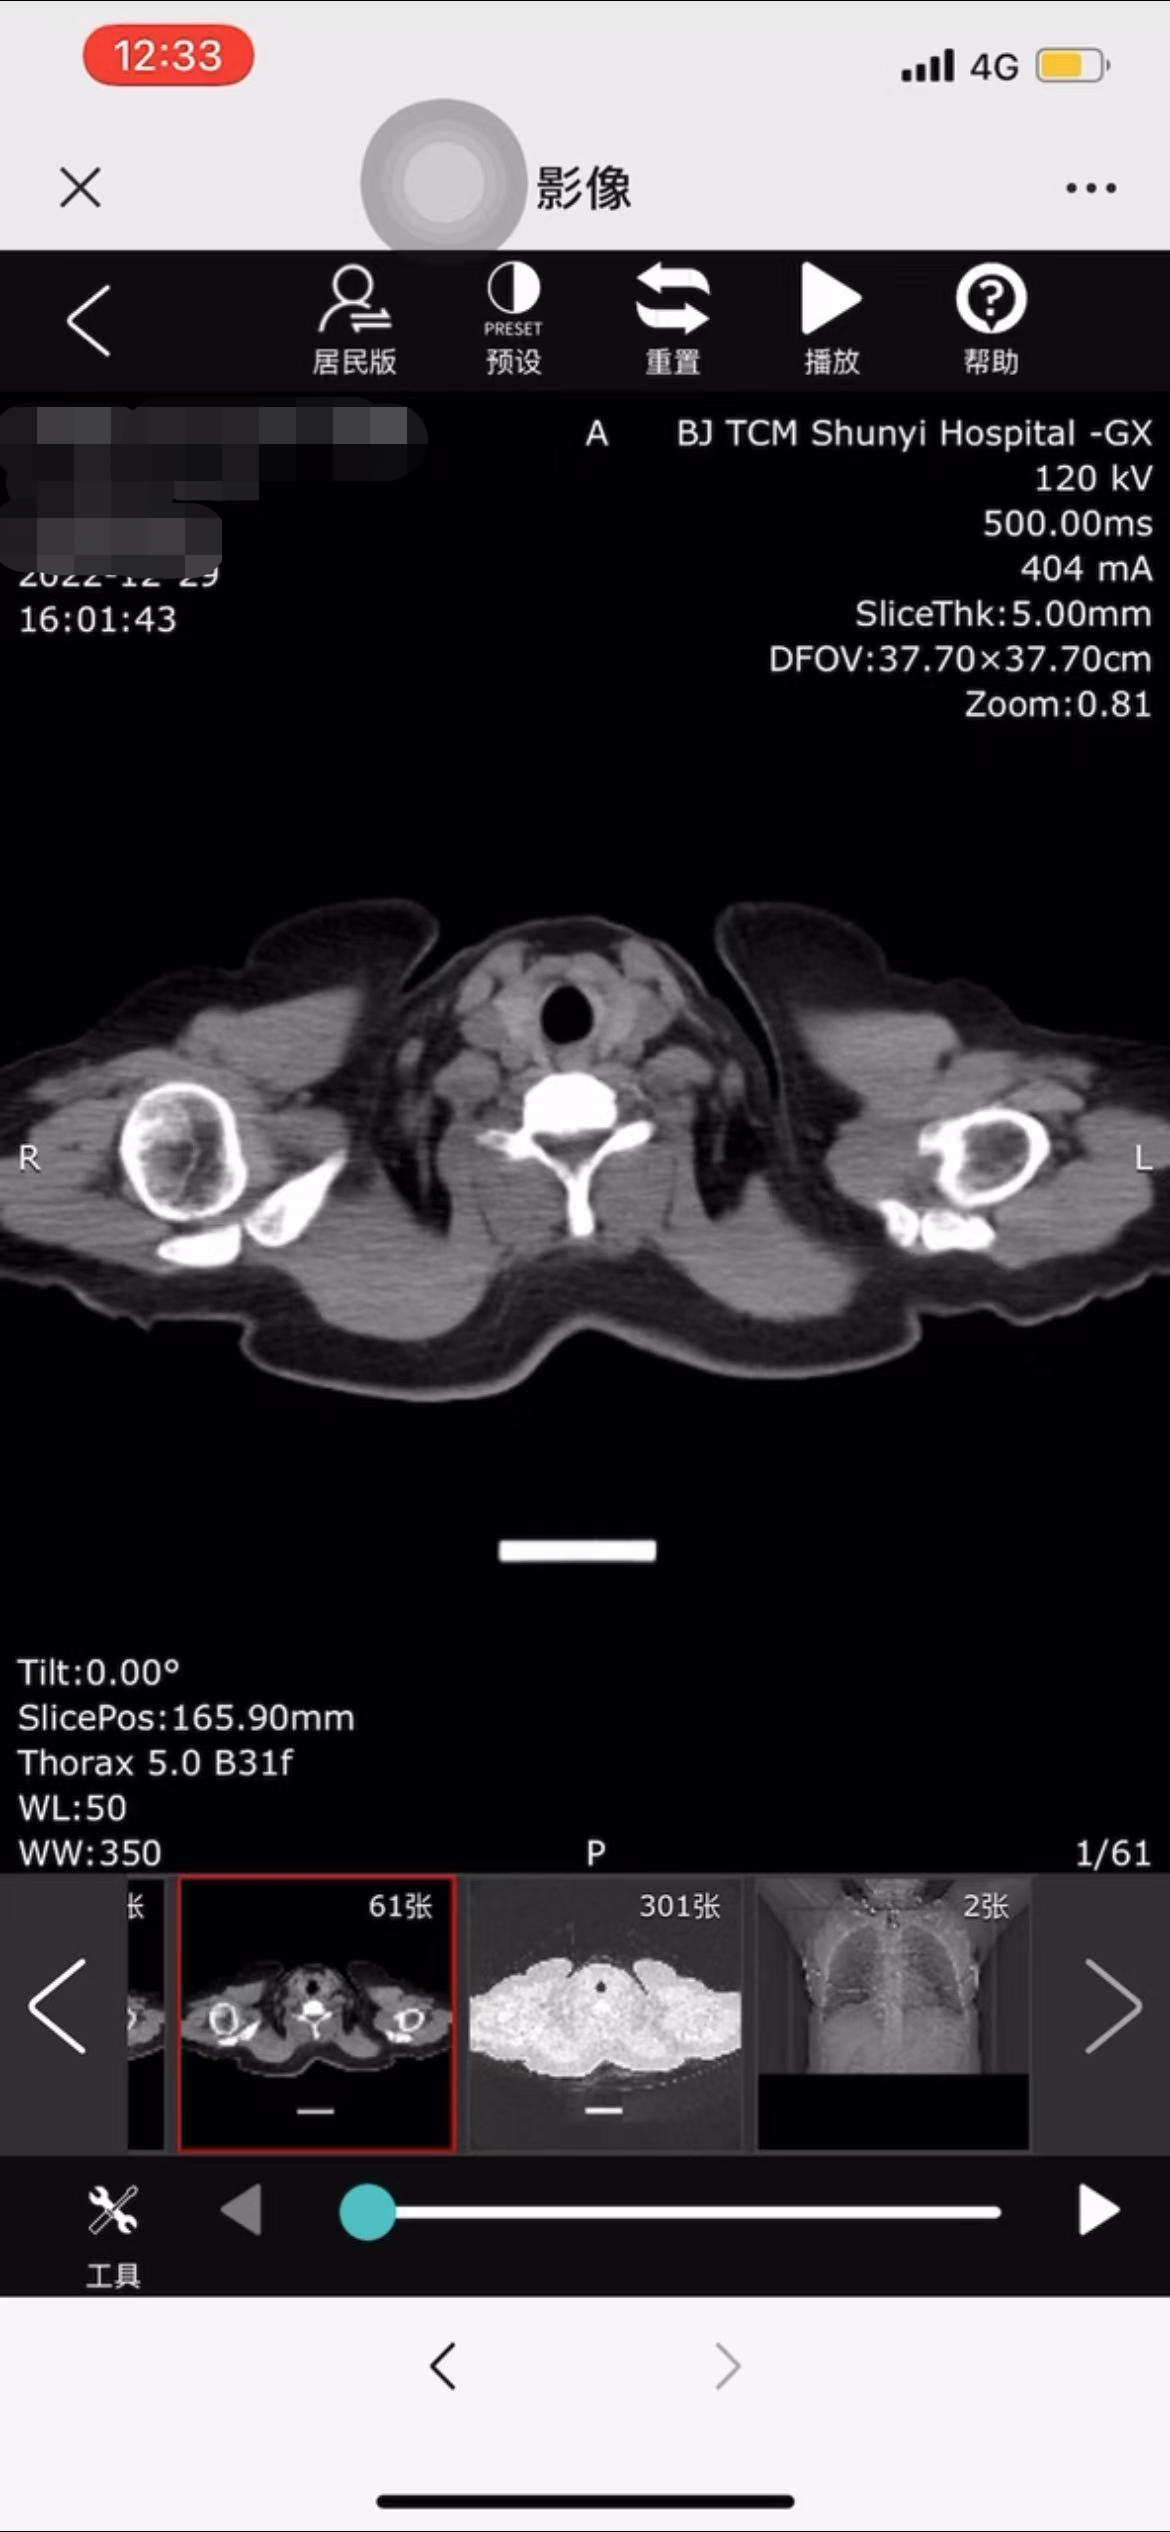

为解决患者排队取片、胶片携带不便、胶片折损丢失、异地转诊或网络问诊无法及时提供影像胶片等困扰,近日,北京中医医院顺义医院微信公众号上线“云胶片”服务,通过手机智能终端可以随时随地查看诊断或分享影像检查资料,有效解决了传统胶片的各种短板问题,大大节省了人力、物力,方便医生问诊的同时,也极大提高了患者的就诊效率,改善了患者的就医体验。

“云胶片”突破了传统胶片对于图像帧数的限制,能够为患者提供此次检查的全部DICOM原始影像,并具备缩放、移动、动态展示等多种图片处理功能,高清晰的原始图像方便患者查看,也更利于医生对病灶情况进行分析,提高诊断效率和精准度。

与传统胶片相比,“云胶片”是存储和共享的数字化胶片,影像报告审核完成后自动传送至云端,可实现即存即取、即用即看。检查完成后,患者无需在医院排队等待打印报告和胶片,只需一部手机,随时随地查看影像报告,还可以将检查结果直接发给亲朋或者异地专家咨询,大大降低时间和人力成本,减少患者在院等候时间。

传统胶片只包含少部分图像,且无法进行参数调节、动态显示,出于病情诊断的需要,到外院就诊时,医生很可能要求患者重新做检查,不仅不方便,费用支出也会相应增加。“云胶片”通过授权可以实现影像数据共享,并支持缩放、移动、动态展示等,极大满足患者异地转诊、远程会诊的需求。